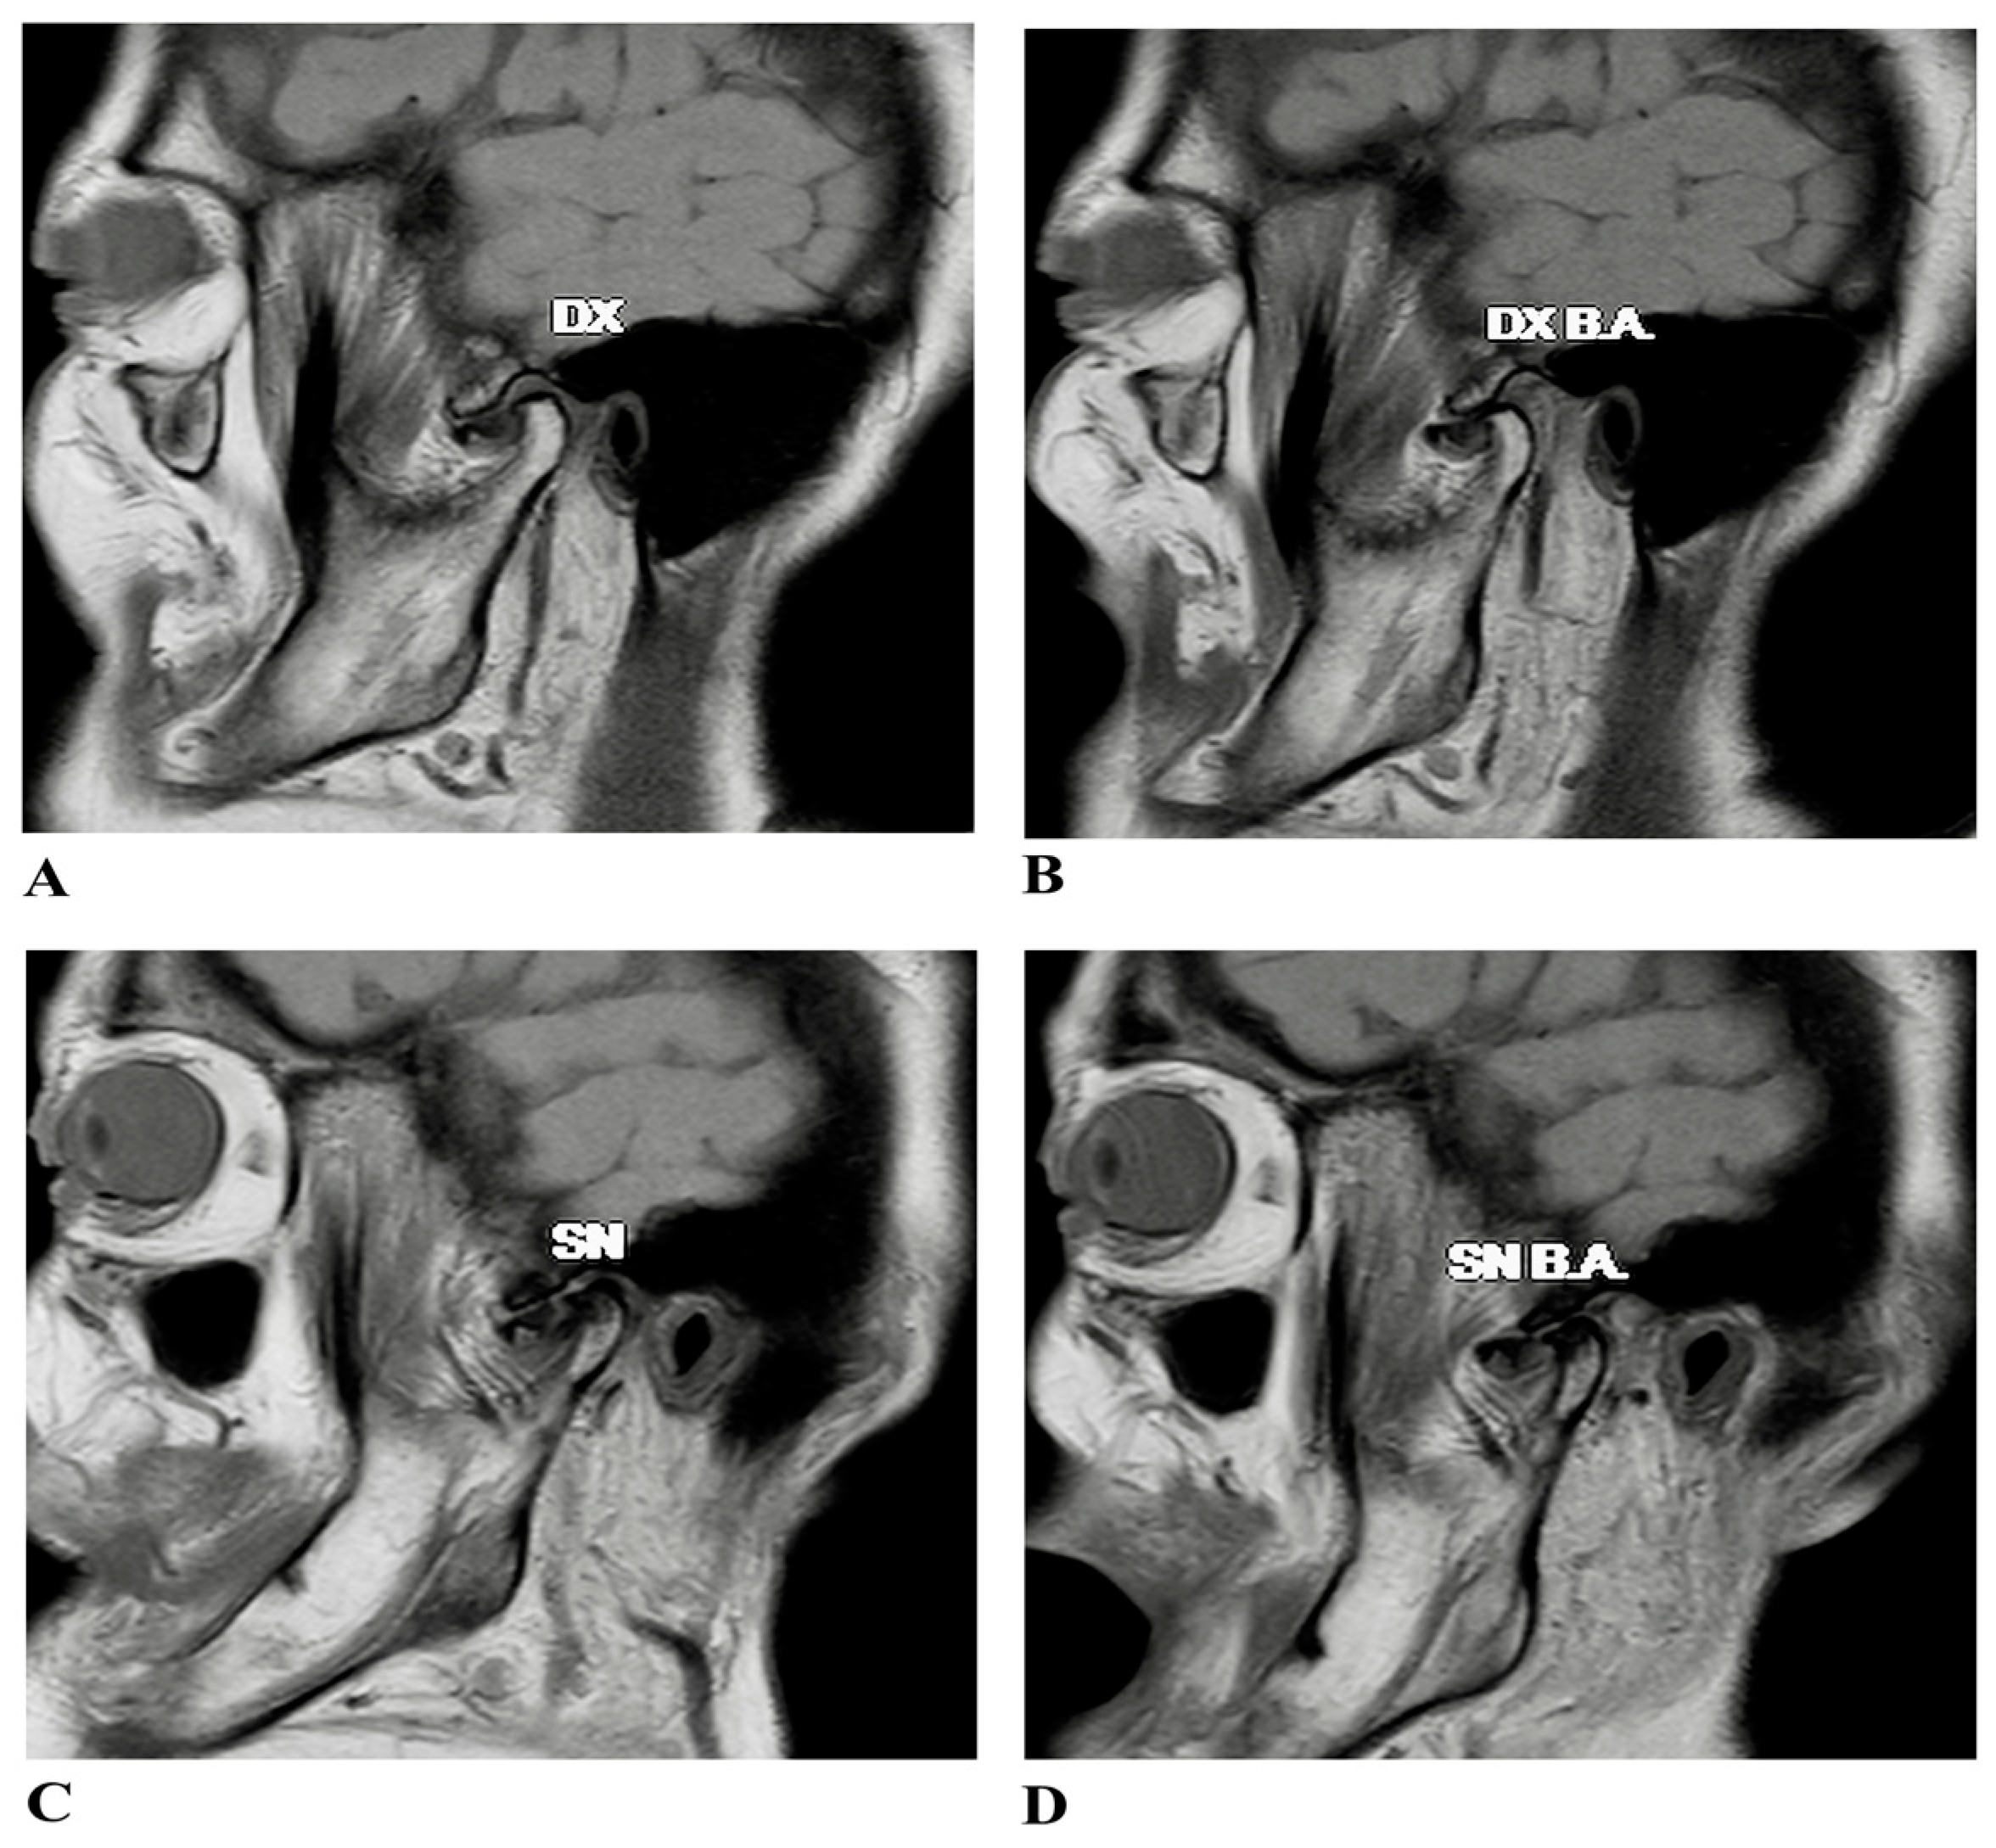

2.1. Case Presentation

2.2. Surgical Treatment